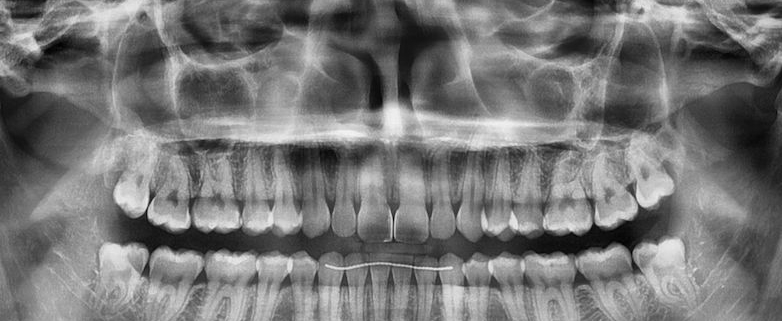

- Réaliser une analyse clinique et radiologique complète avant une extraction complexe

- Analyse pre-opératoire et lecture du Cone Beam (CBCT)

- Dents de sagesse : classification, difficultés et stratégie chirurgicale